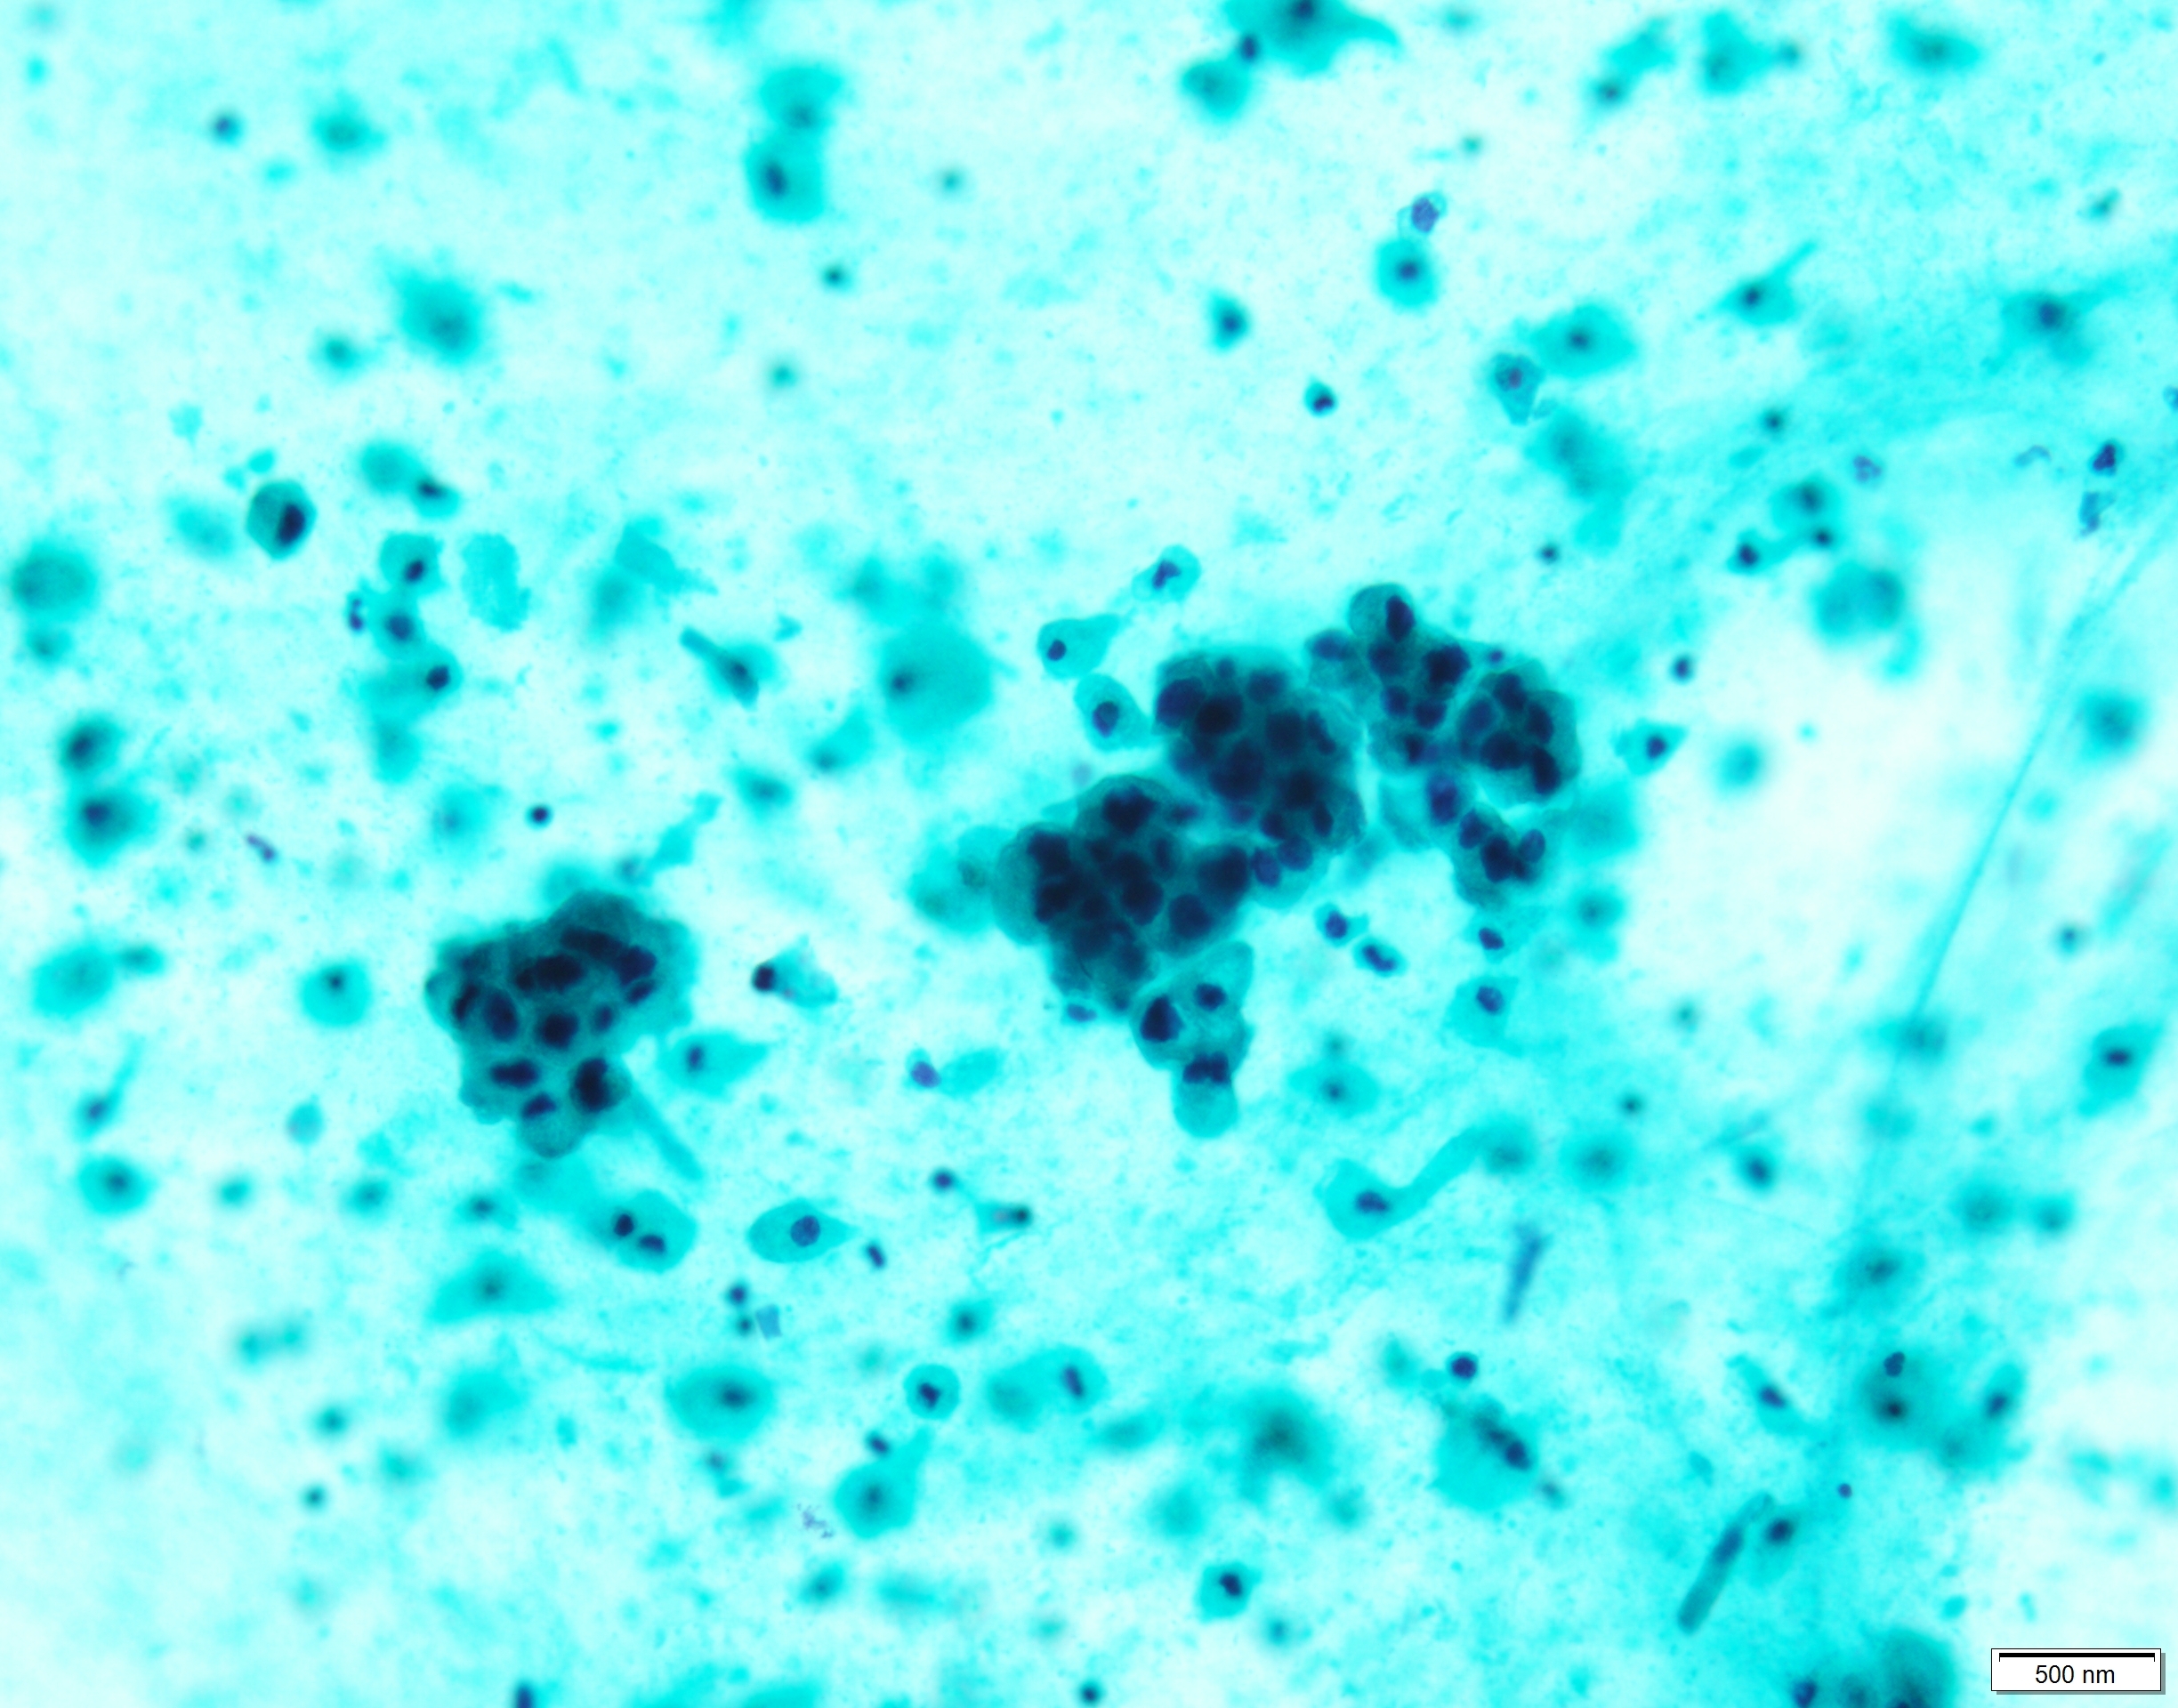

Pap×20